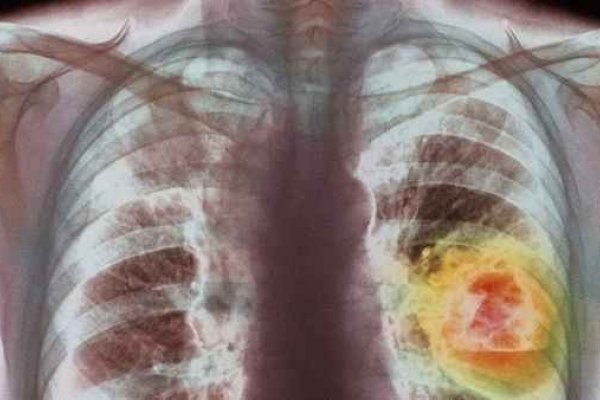

Međutim, sada su naučnici predstavili istraživanje u kojem su otkrili kako su konzumenti ovakvih vrsta cigareta u većem riziku od dobivanja raka.

Light cigarete, sa rupicom u sredini su još prije 50 godina predstavljene kao zdravija verzija cigareta, ali ove rupice omogućuju konzumentima da udišu veću količinu dima od cigareta, dima koji sadrži visoke nivoe hemikalija i toksina.

Upravo ova rupica omogućava cigareti da brže gori i tako stvara više kancerogena koji dolaze do ljudskih pluća.